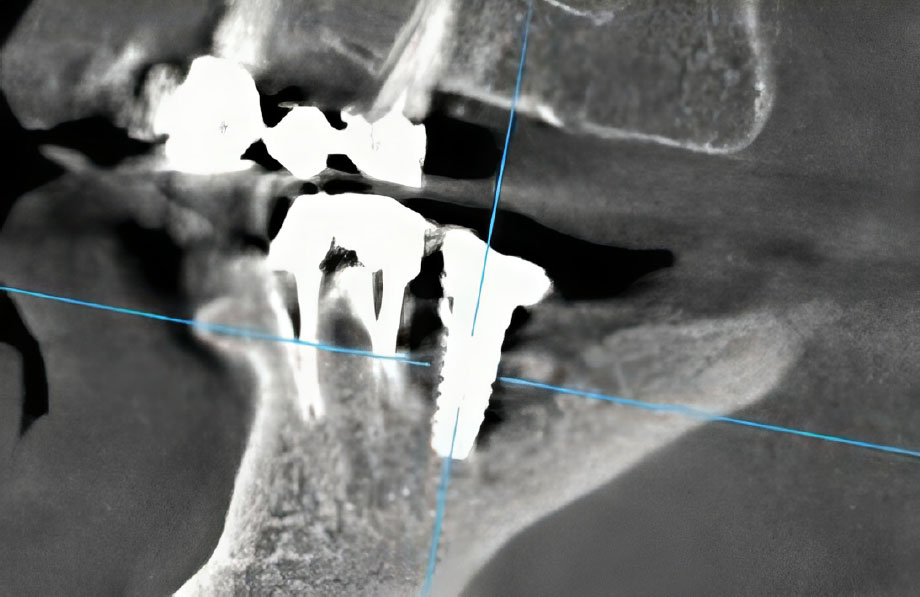

Intraoral examination revealed localized gingival erythema and edema in the area of teeth #45 and #46. Palpation was painful and elicited a purulent discharge from the peri-implant sulcus of #46. Periodontal probing detected deep pockets (>8mm) with palpable, rough, and exposed bone. Notably, the dental implant at site #46 was initially clinically stable. Cone-Beam Computed Tomography (CBCT) imaging revealed a sclerotic bone pattern with increased bone density surrounding the implant, along with a distinct focus of bone destruction adjacent to the implant apex at site #46, consistent with osteonecrosis (Figs. 1, 2). Based on the AAOMS diagnostic criteria, a diagnosis of Stage 2 Medication-Related Osteonecrosis of the Jaw (MRONJ) was established.

Coronal CT projection showing increased bone density surrounding the implant in the right mandible compared to the contralateral side (preoperative baseline).